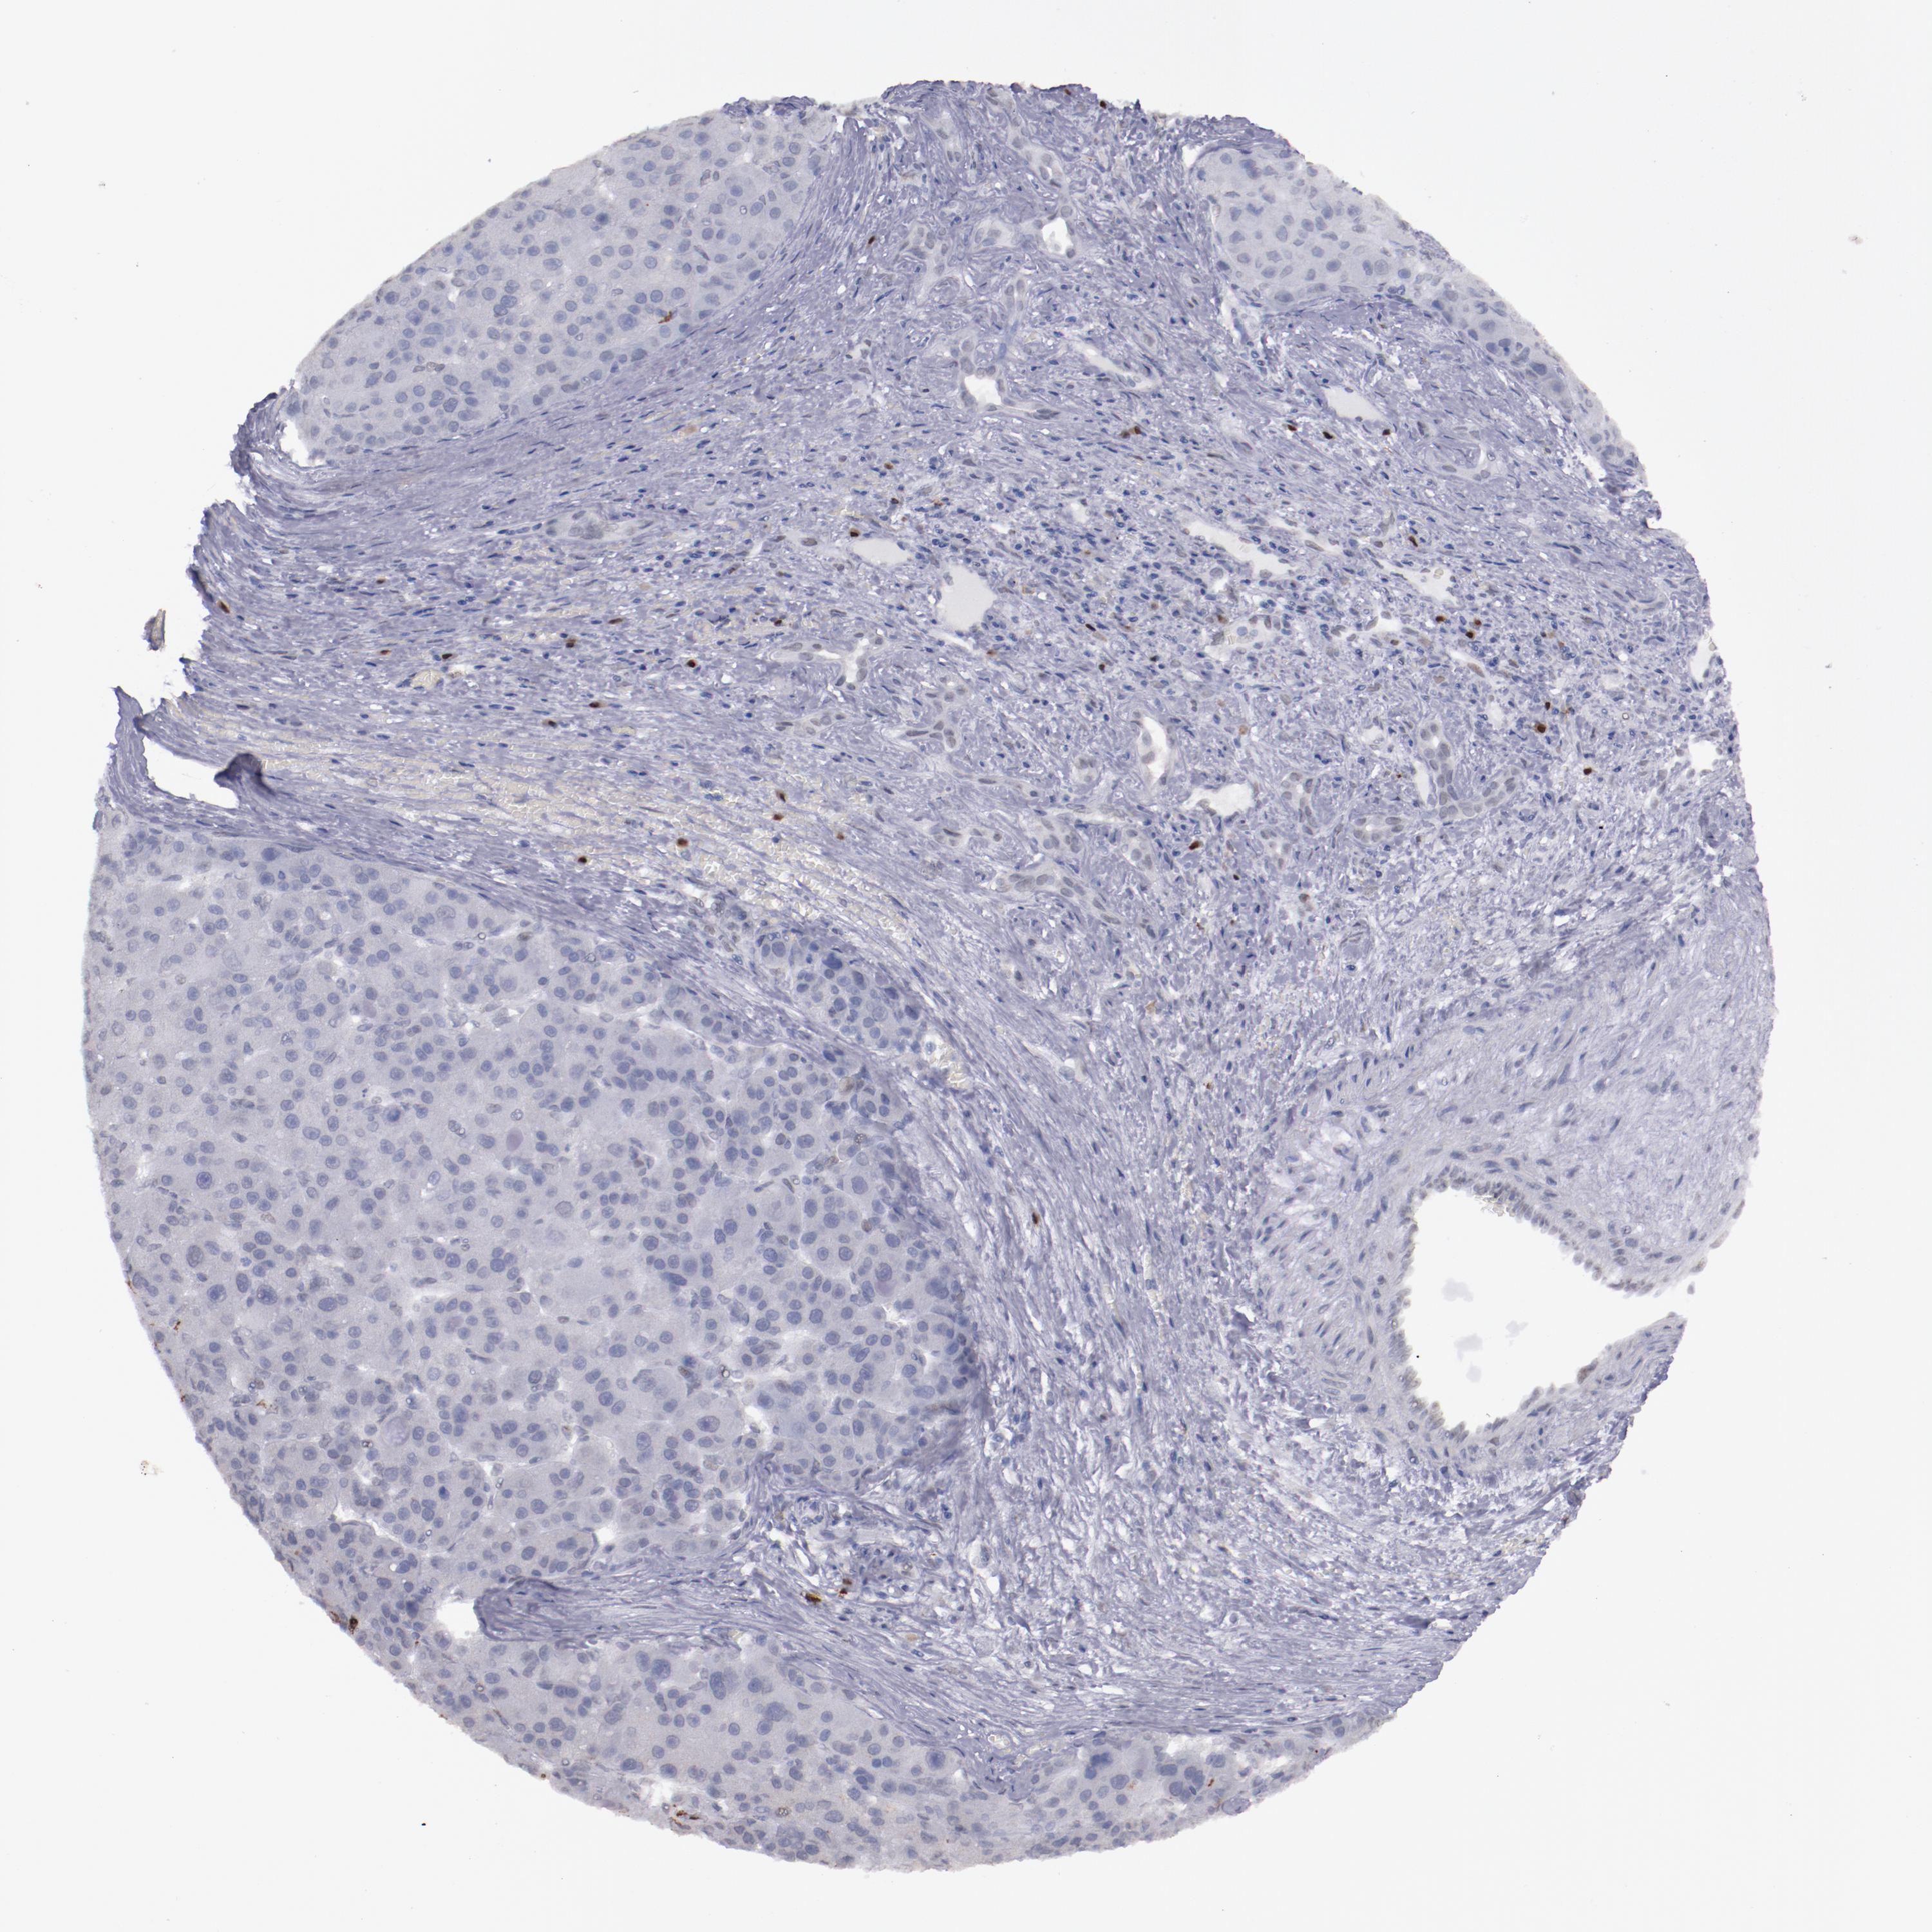

LIVER CANCER - Protein expressioni

A mouse-over function shows sample information and annotation data. Click on an image to view it in a full screen mode. Samples can be filtered based on level of antibody staining by selecting one or several of the following categories: high, medium, low and not detected. The assay and annotation is described here.

Note that samples used for immunohistochemistry by the Human Protein Atlas do not correspond to samples in the TCGA dataset.

Antibody stainingi

Antibody staining in the annotated cell types in the current human tissue is reported as not detected, low, medium, or high, based on conventional immunohistochemistry profiling in selected tissues. This score is based on the combination of the staining intensity and fraction of stained cells.

Each image is clickable and will lead to virtual microscopy that enables deeper exploration of all samples and also displays staining intensity scores, fraction scores and subcellular localization as well as patient and tissue information for each sample.

Antibody HPA002038

Antibody HPA002698

Antibody CAB013508

Staining

High

Medium

Low

Not detected

Intensity

Strong

Moderate

Weak

Negative

Quantity

>75%

75%-25%

<25%

None

Location

Nuclear

Cytoplasmic/membranous

Cytoplasmic/membranous,nuclear

Cholangiocarcinoma

Carcinoma, Hepatocellular, NOS